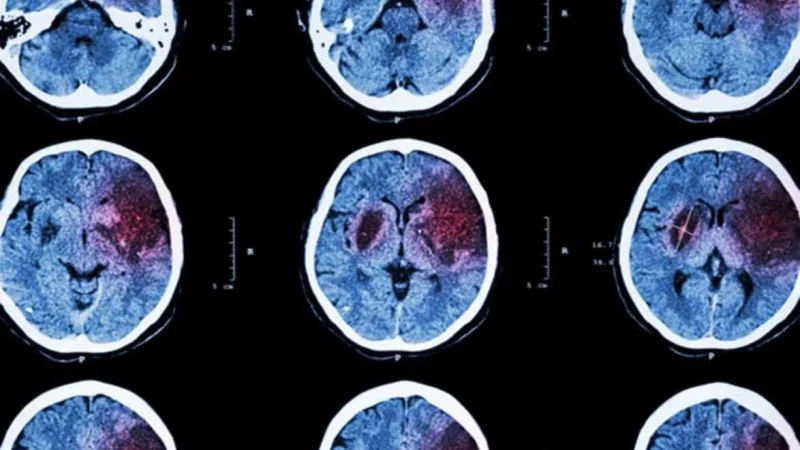

Circulan contenidos que utilizan un video de Canal Sur Almería en España, sobre el aumento de casos de ictus en jóvenes para vincular el incremento con las vacunas contra la COVID-19.

Sin embargo, el aumento del 40% en estos casos se recoge en datos hospitalarios entre 2010 y 2022, por lo que la tendencia comenzó antes de la pandemia y de la campaña de vacunación.

Patricia Mar Martínez, médica del Hospital Torrecárdenas y entrevistada en el video, ha explicado a Maldita.es (medio integrante de la Red LATAM Chequea) que la tendencia no ha cambiado con la COVID-19 y que el incremento de ictus -también conocidos como derrames cerebrales- responde a factores como el sedentarismo y el consumo de drogas.